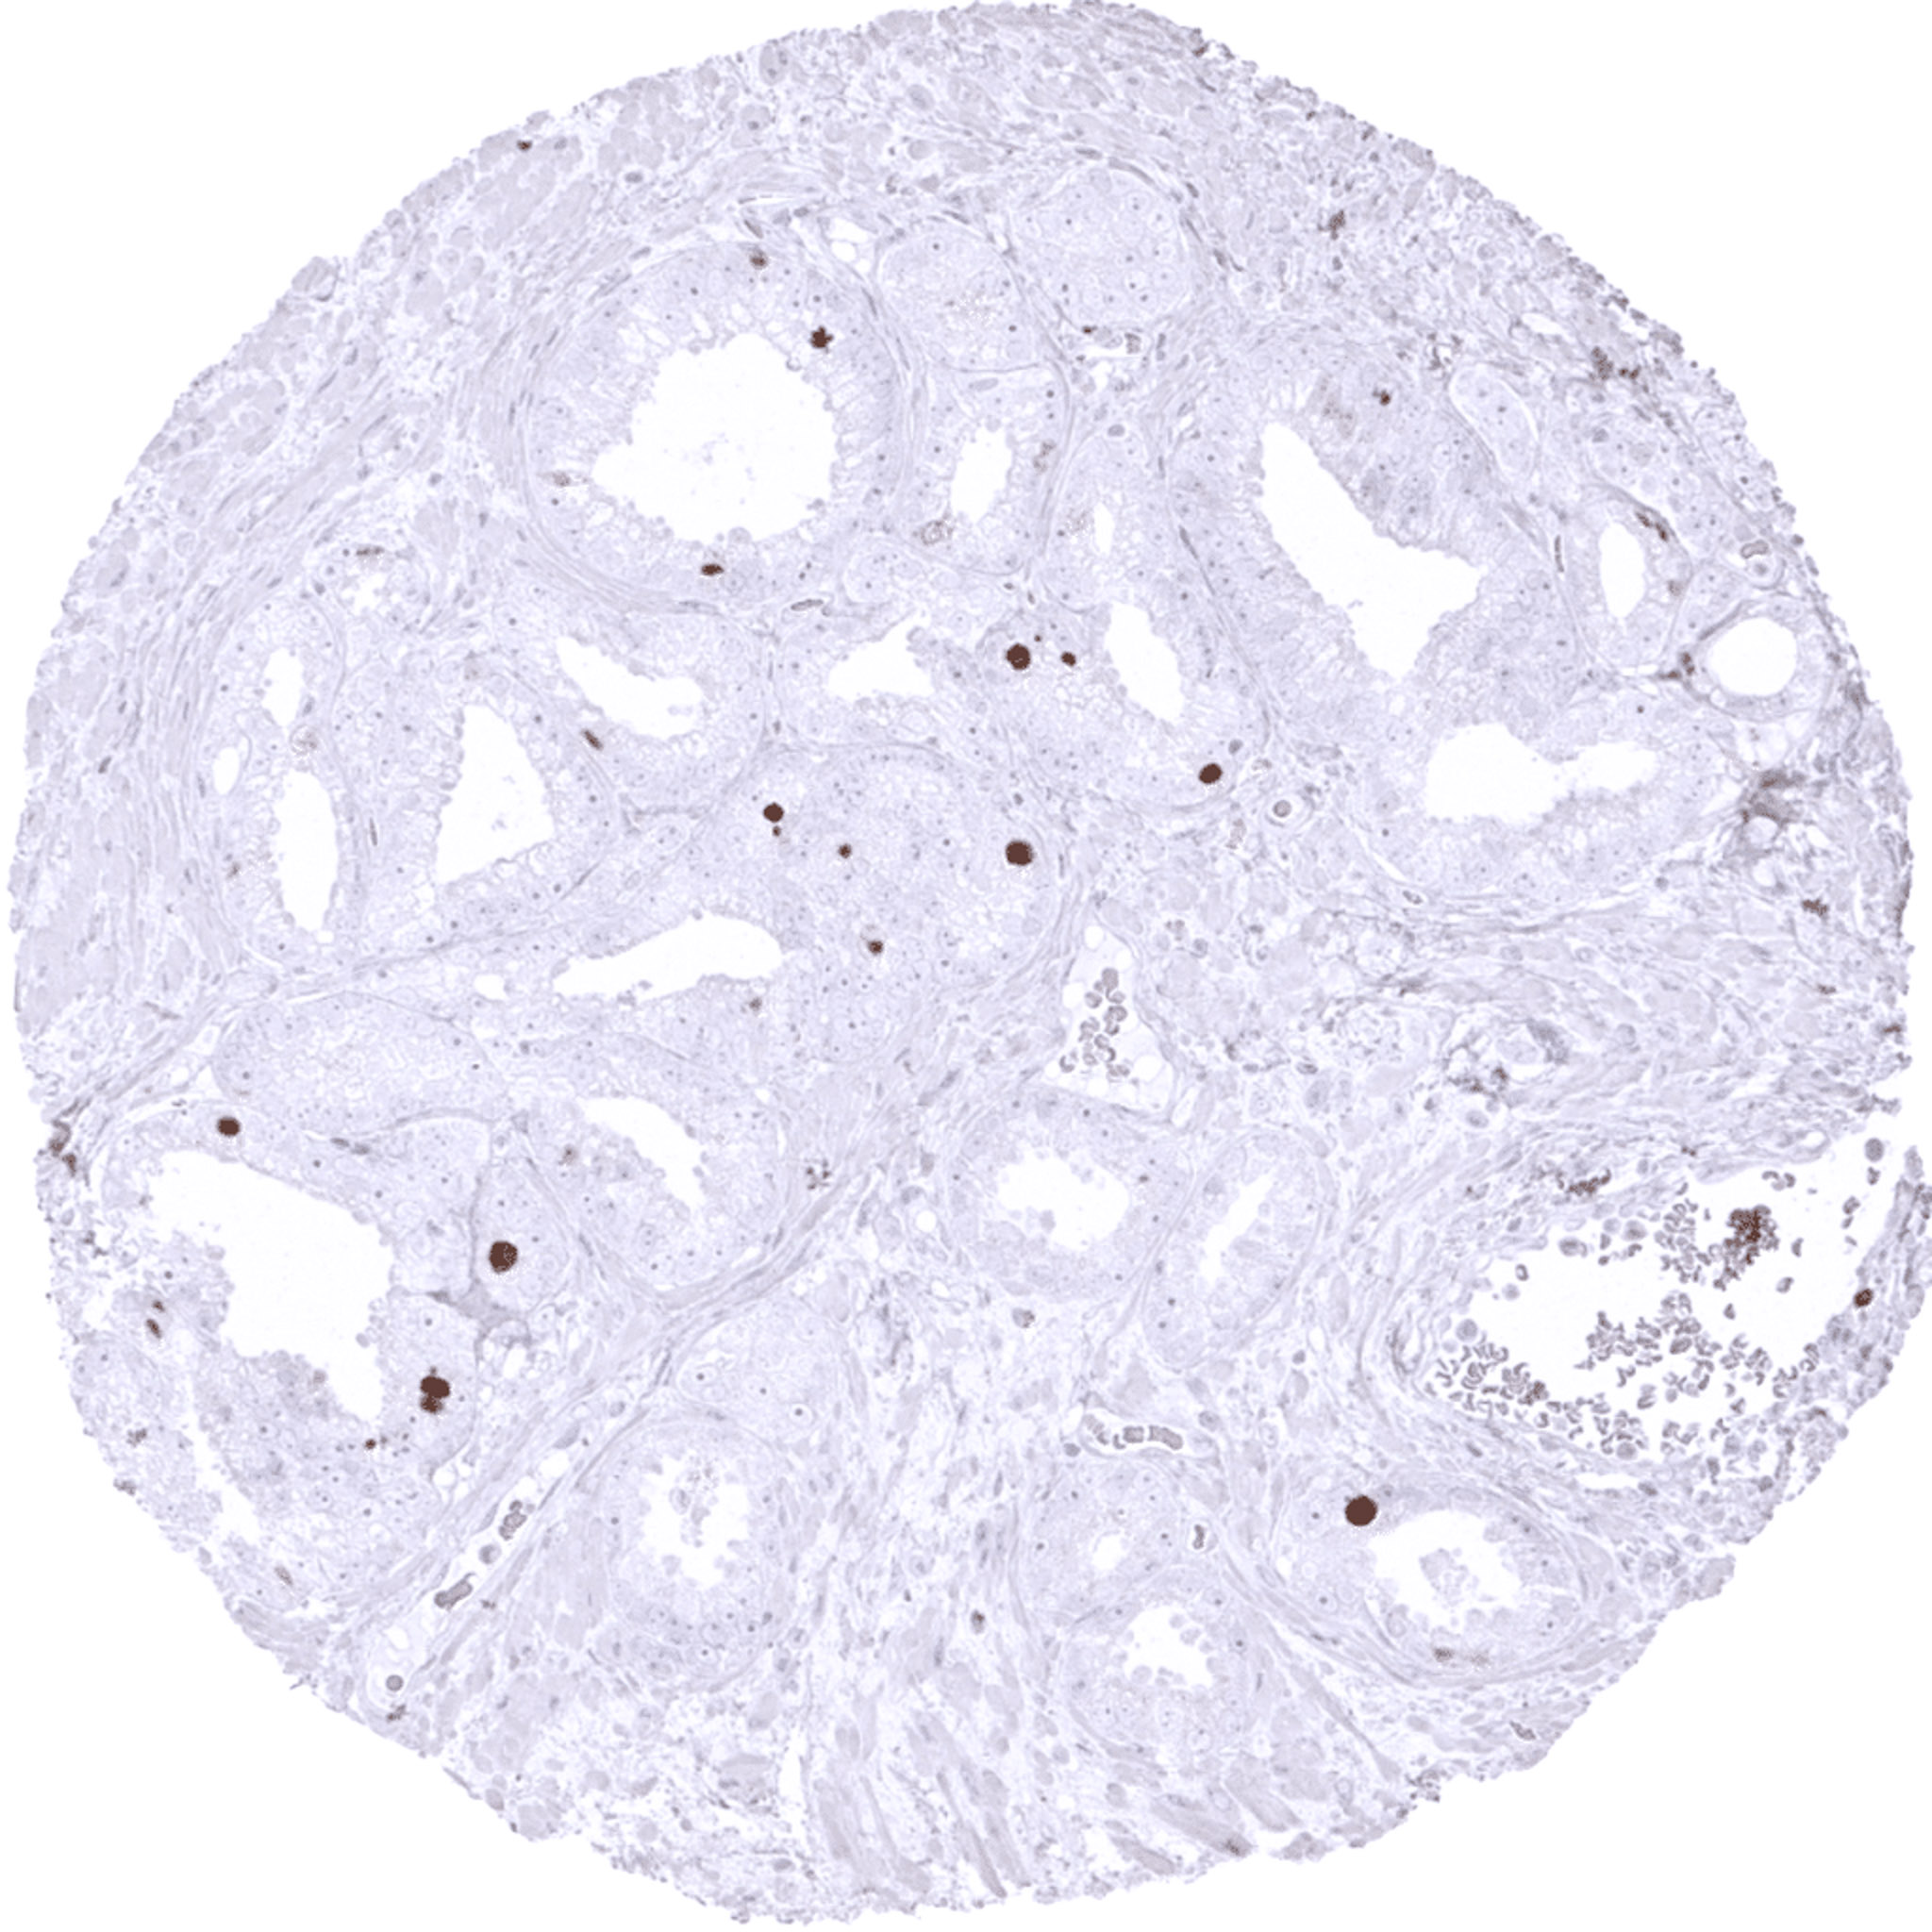

Thyroid – Follicular carcinoma with Topoisomerase II alpha immunostaining in about 1% of tumor cells.